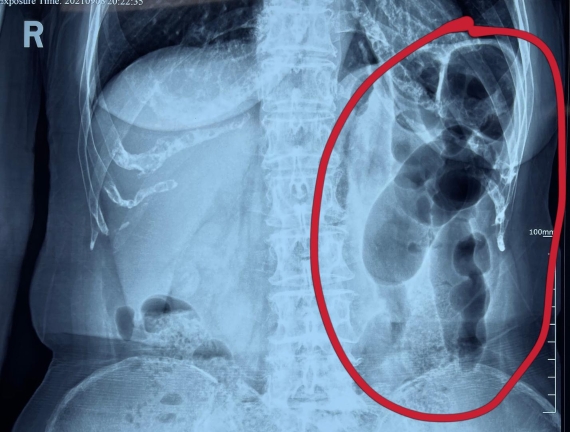

據(jù)省醫(yī)院消化病院消化二科姜子曄醫(yī)生介紹,韓大娘今年已經(jīng)73歲,家住哈爾濱市,一周前開始腹脹腹痛,有較為明顯的左側(cè)腹部疼痛,疼痛劇烈時會出現(xiàn)左側(cè)腹部鼓包情況,排氣排便后有所好轉(zhuǎn)。韓大娘家人見狀將其送到了黑龍江省醫(yī)院,門診檢查腹部平片提示為左側(cè)腹部積氣,口服全消化動力藥及通便治療后腹痛腹脹有所緩解,入院前再次突發(fā)左側(cè)腹痛加重伴有明顯腹脹,急診隨后以“腹痛腹脹原因待查”將韓大娘收入到消化病院消化二科。

姜子曄醫(yī)生熱情接待了韓大娘,為其進(jìn)行了仔細(xì)查體,除了左側(cè)腹部壓痛并未見明顯異常,對癥給予灌腸后,韓大娘的腹脹有所緩解,第二天姜子曄醫(yī)生為韓女士進(jìn)行了胃腸鏡檢查,也未見明顯異常。但此時韓大娘腹部平片結(jié)腸腸管擴張仍然很嚴(yán)重,腹痛腹痛也沒緩解,到底什么原因呢?消化二科主任陸以霞在查房時建議繼續(xù)給予韓大娘口服全消化動力藥,必要時灌腸治療,同時陸以霞主任在追問病史查體時發(fā)現(xiàn)韓大娘左下腹紅色皮疹和小水泡,反復(fù)抓撓腹部皮膚部分已結(jié)痂,高度懷疑為帶狀皰疹。